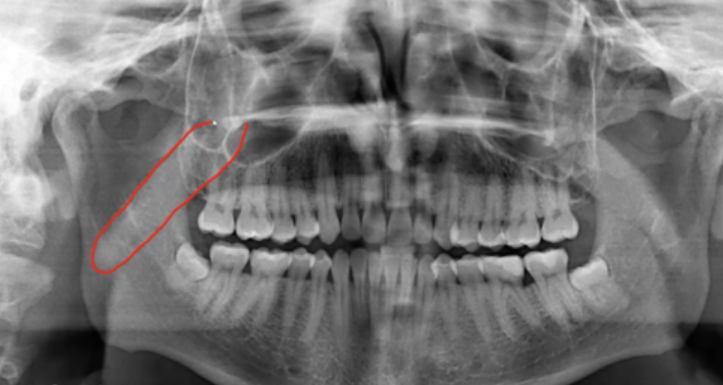

red - zygomatic process of maxilla

blue - zygoma